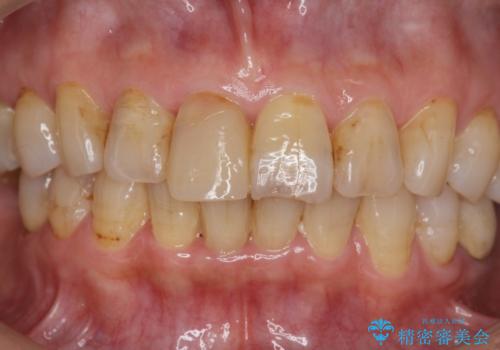

透明感や周囲の歯との色の調和に大変ご満足いただけました。

色調の変化が少なく、長期的な予後を見込めるジルコニアクラウンで天然歯を模した審美性の回復を計画します。

当法人でご提案できる最上位クラスのジルコニアクラウンです。